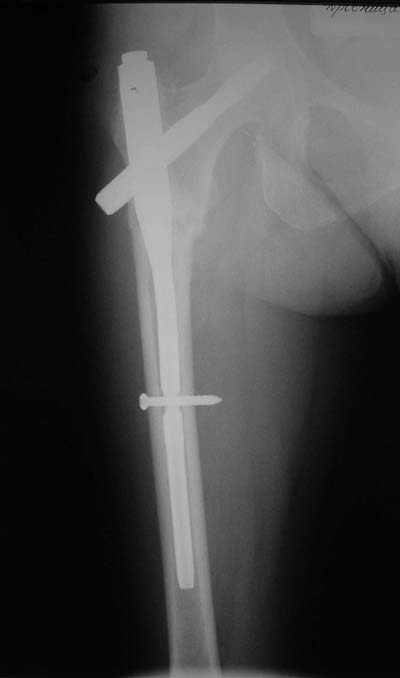

Не думаю так. см вложение.

>> короткий штифт какой-то неуютный выбор.

> Не думаю так. см вложение.

Для такого перелома вполне может быть использован диафизарный штифт, который отечественного производства я даже боюсь считать во сколько раз дешевле... Недавно несколько примеров я закидывал.